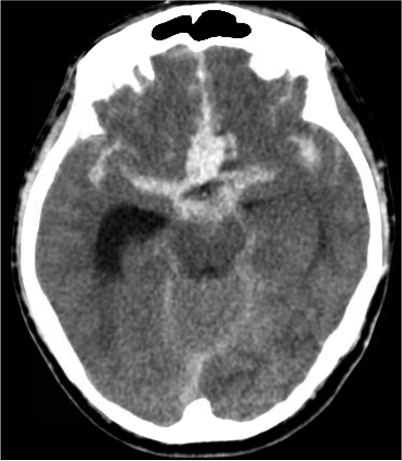

The image to the right is a CT scan showing subarachnoid hemorrhage from a brain aneurysm rupture. The bright white border is the skull. The gray substance is the brain. The bright areas inside the brain that’s not as white as the skull is the subarachnoid hemorrhage blood in the brain.